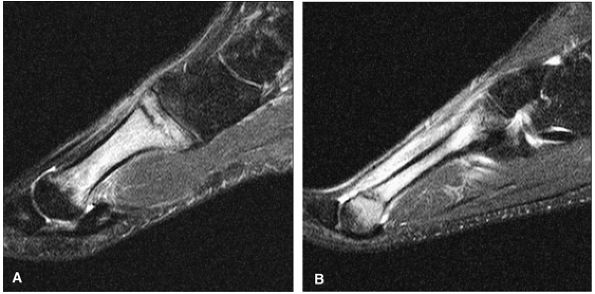

FIGURE 5.95 ● Stage I OLT with subchondral bone marrow edema, which is hypointense on the coronal T1-weighted FSE image (A) and hyperintense on the coronal FS PD FSE image (B). The overlying talar articular cartilage is hyperintense on the FS PD FSE image (B).